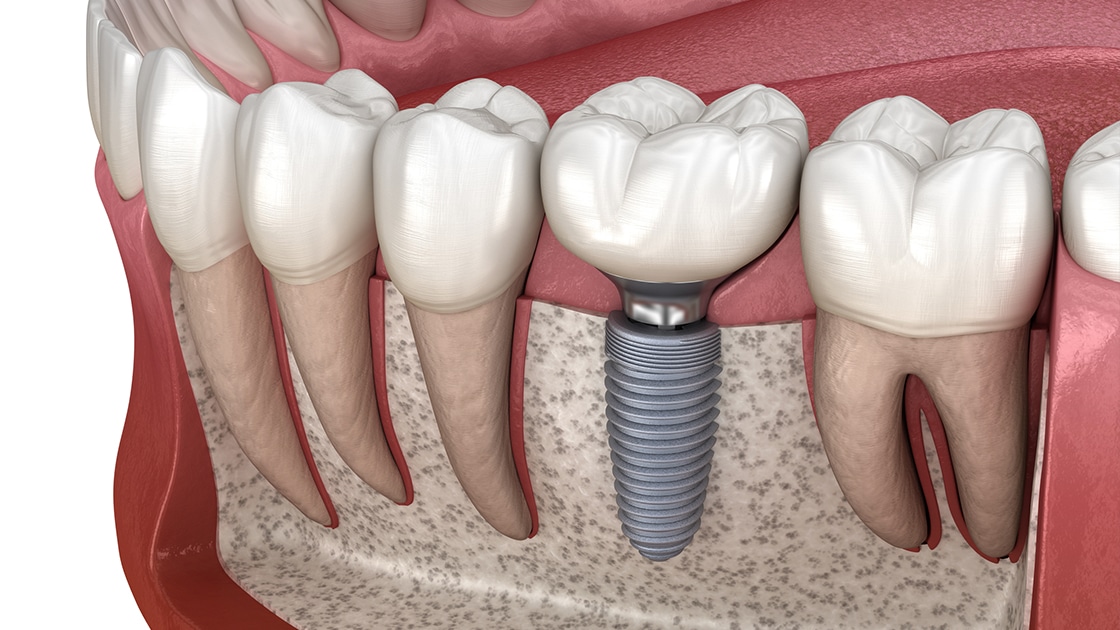

Phase 4: Implant Surgery

During the surgical stage, the titanium post (serving as the artificial root) is inserted into the jawbone. This is a minor surgical procedure performed under local anaesthetic. The surgery usually takes one to two hours per implant. After placement, the gum is sutured around the implant to promote healing.

Phase 5: Healing and Osseointegration

This healing period—known as osseointegration—is when the implant fuses with the jawbone. It is the longest stage, typically lasting three to six months. A temporary crown or denture may be fitted during this time to maintain aesthetics and function. Proper care and hygiene are essential to ensure successful integration.

Phase 6: Abutment and Final Restoration

Once the implant has fully integrated, an abutment is attached. This component serves as the connection between the implant and the final crown. After a short healing period following abutment placement, the permanent crown, bridge, or denture is secured, completing the restoration. This phase brings back full chewing function and a natural appearance.